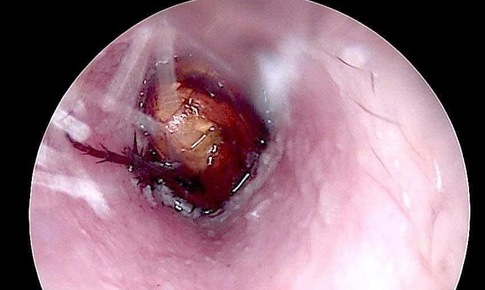

Loại bỏ khối u chung sống 10 năm gây liệt mặt

Camera bệnh viện - 08/10/2025 17:16SKĐS - Các bác sĩ Bệnh viện Tai Mũi Họng Trung ương đã thực hiện ca phẫu thuật, loại bỏ trọn vẹn khối u và bảo tồn tối đa chức năng, thẩm mỹ vùng mặt cho người bệnh.